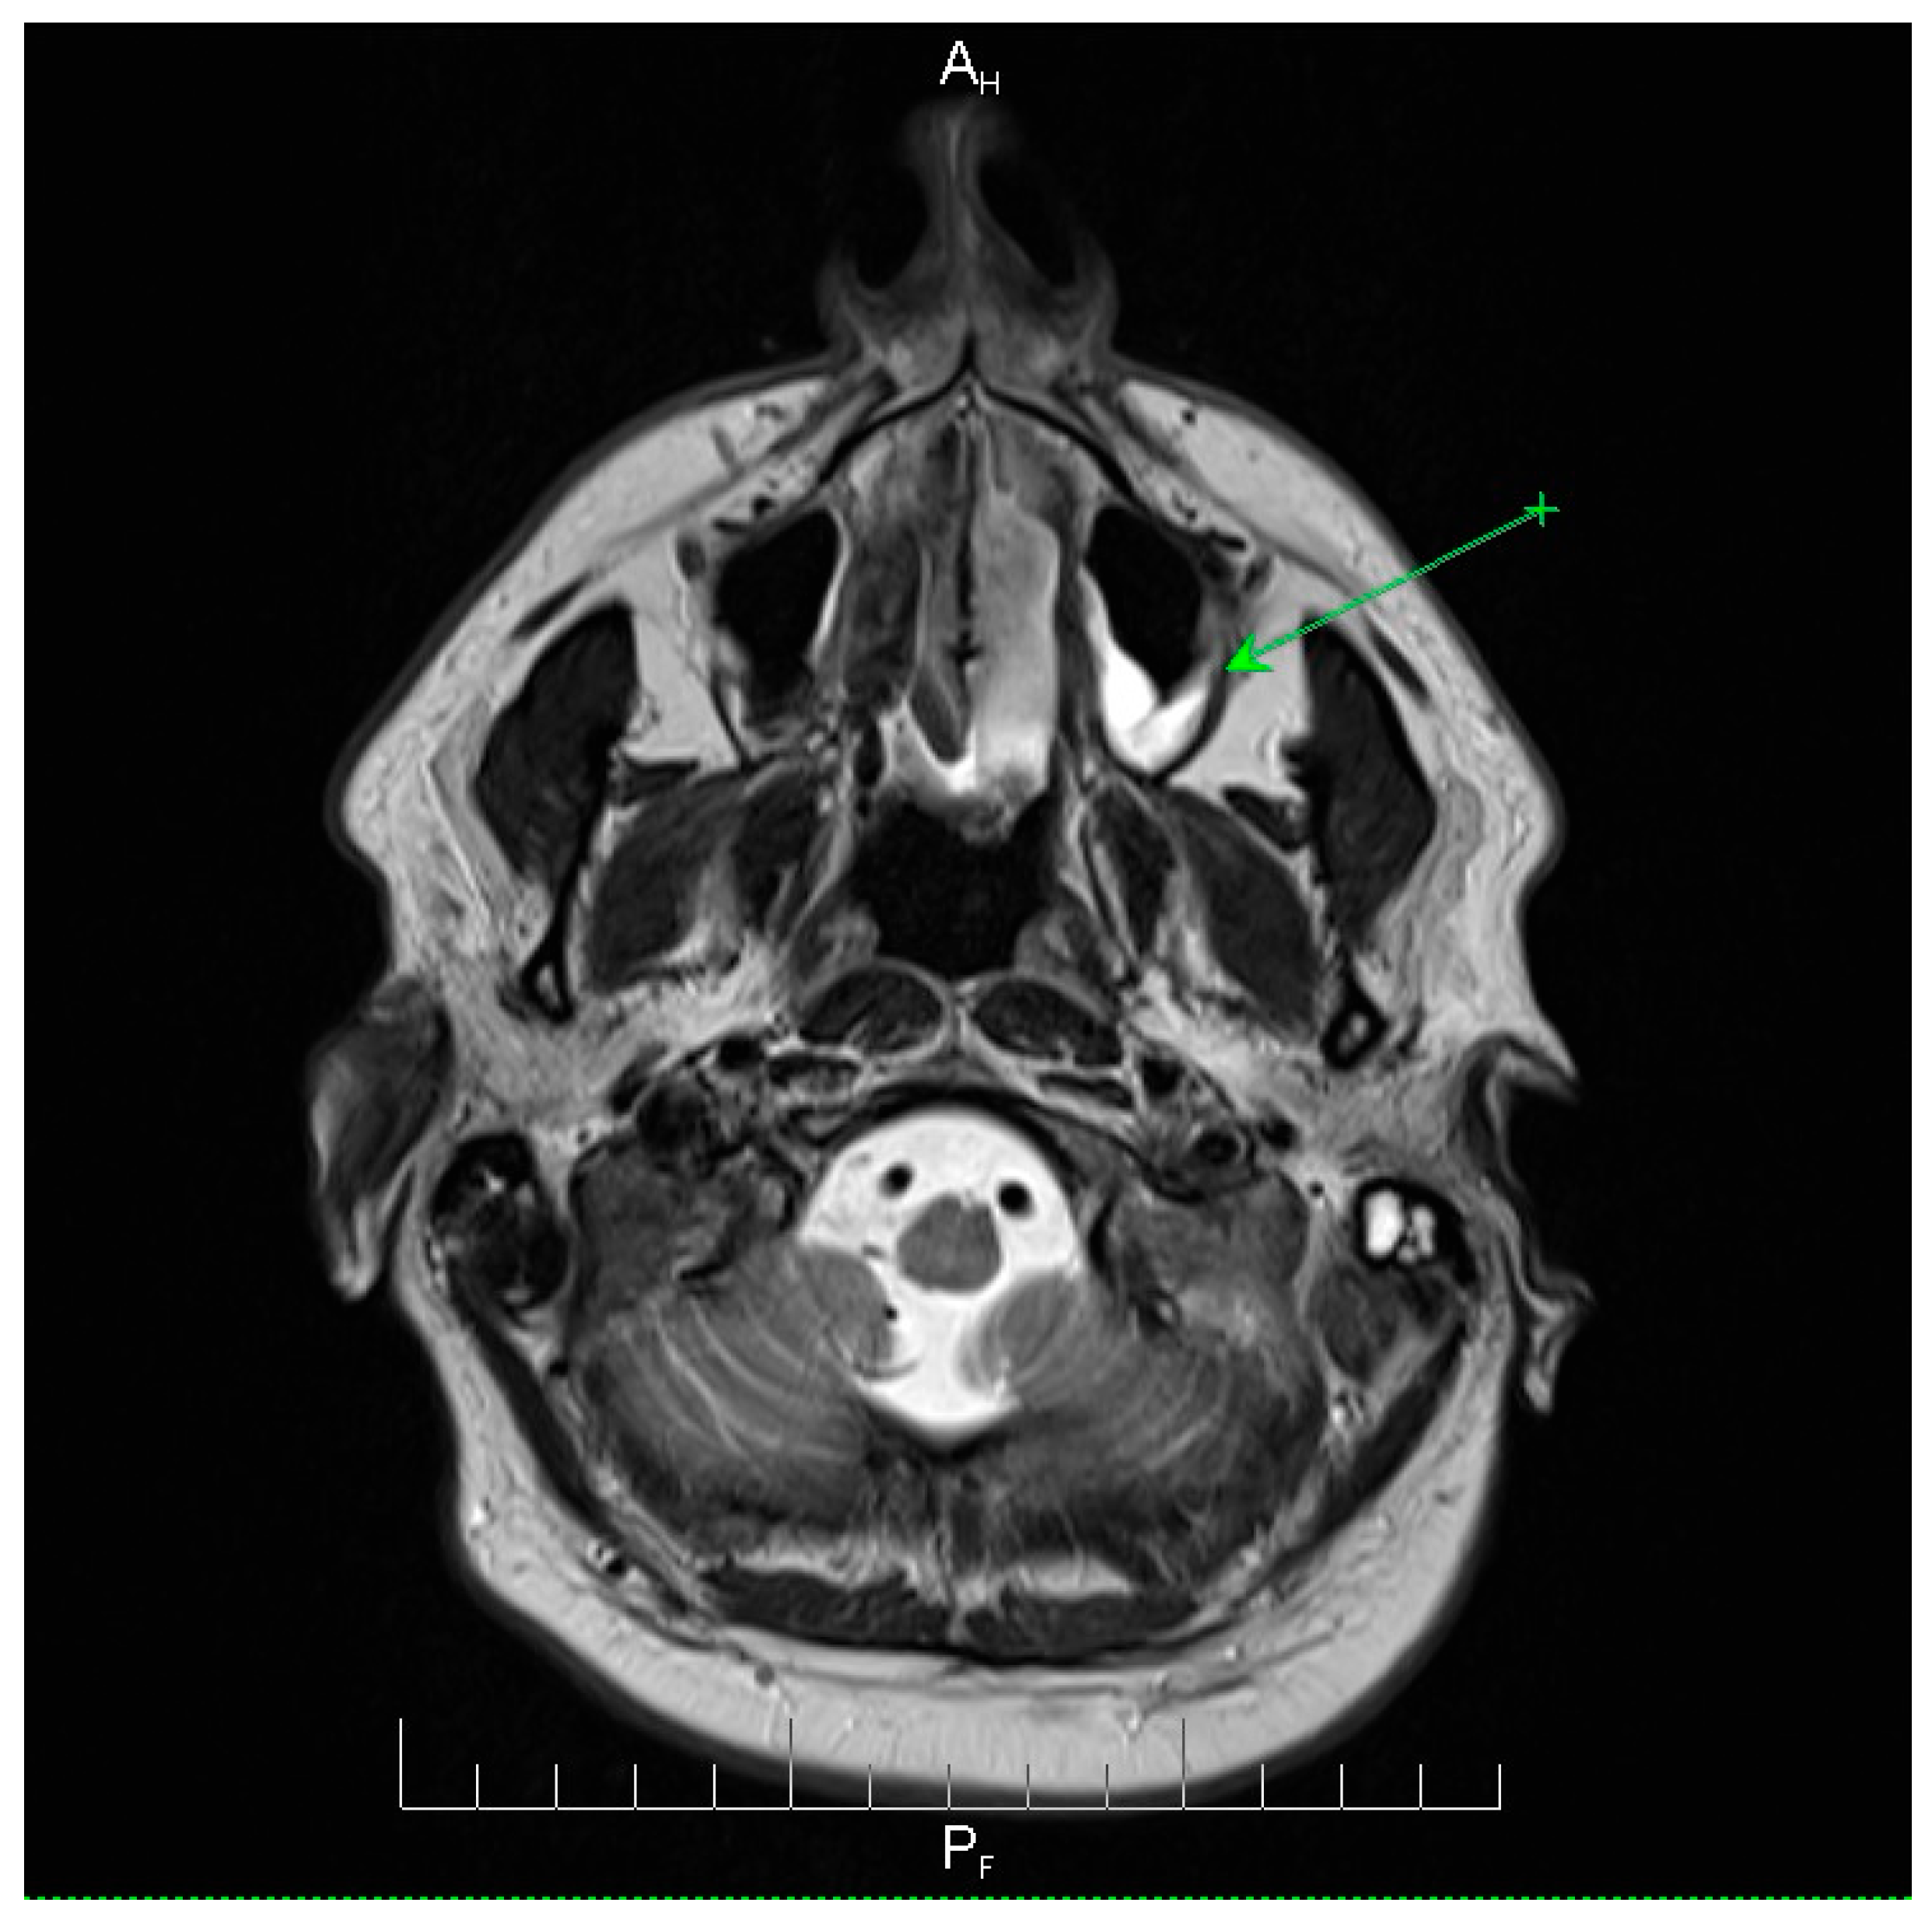

Neuroimaging revealed mild ethmoidal/sphenoidal sinus opacification and left mastoid air cell involvement without evidence of parenchymal lesions or venous sinus thrombosis (Figure 1, Figure 2 and Figure 3). Coronal and axial T2-weighted MRI sequences revealed para-fluid collections within the left mastoid air cells extending toward Citelli’s angle (Figure 1, Figure 2 and Figure 3), consistent with an otogenic focus and a possible contiguous route for intracranial spread.

Figure 2.

Axial T2-weighted MRI scan demonstrating opacification of the left mastoid air cells with a hyperintense signal (green arrow), indicative of mastoid involvement. This finding suggests a potential contiguous source of intracranial infection in this patient. No acute lesions, hemorrhage, or signal abnormalities were observed in the cerebellum or brainstem, and the surrounding brain parenchyma appeared normal. These imaging features support localized mastoid pathology without evidence of intracranial extension, providing important radiological context for the patient’s clinical presentation and aiding in the assessment of the infection risk. AH = anterior-head. PF = posterior- foot.